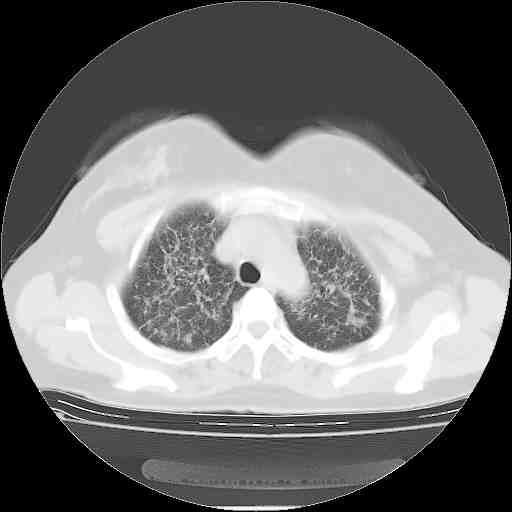

下面是今天刚刚做的,在上海治疗,吃了家属也说不清的一种药,一个月1万左右,

考虑  腺癌肺内转移,治疗较前病灶缩小、减少

支持肺癌并肺内淋巴管转移,

支持肺癌并肺内淋巴管炎,  原发灶小了,但转移较前片明显了.

支气管血管束粗而乱,考虑肺癌肺内淋巴管转移,右侧乳房第一二层软组织成份较左侧多,不会有问题吧?

支持右肺下叶周围型肺癌并肺内淋巴管炎,  原发灶小了,但转移较前片明显了.。

标准的细支气管肺泡癌呀!治疗后病情有所控制,也没治愈的迹象!